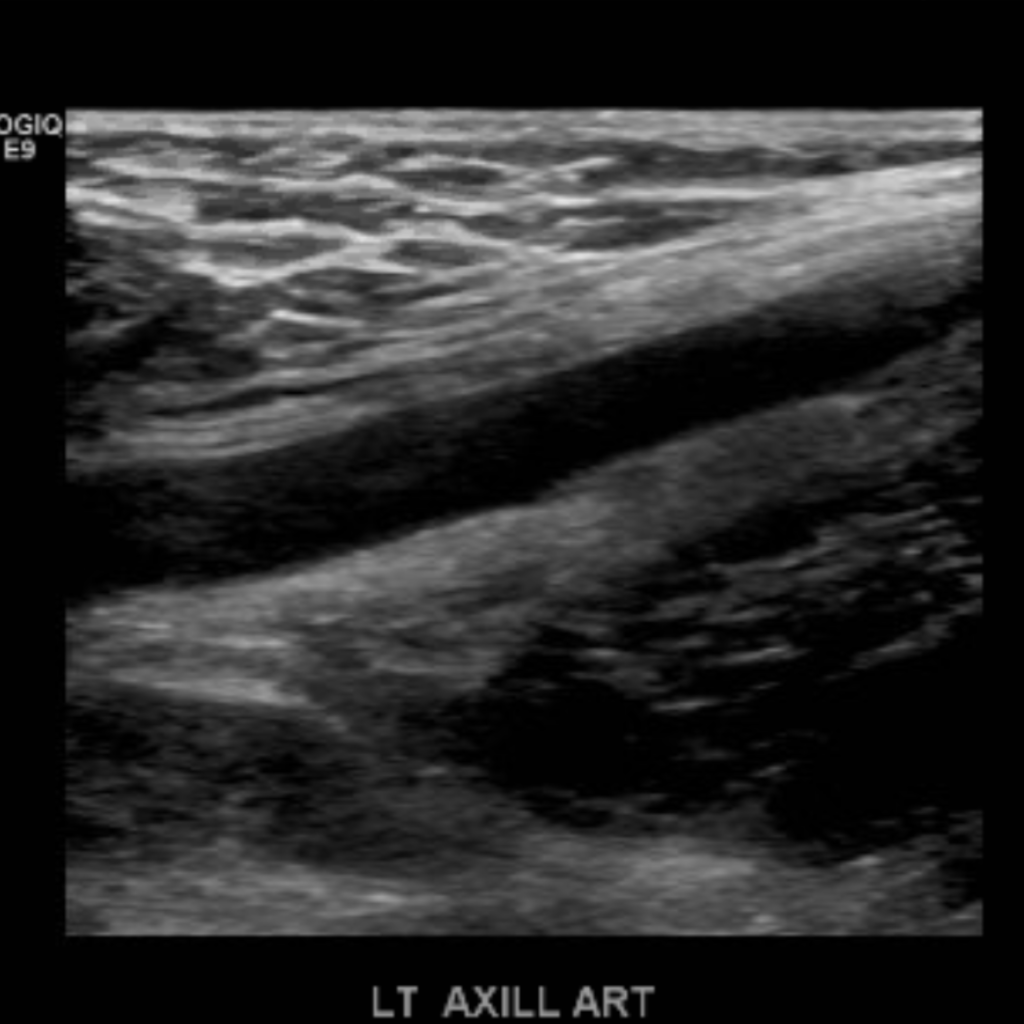

The subclavian artery arises from the brachiocephalic artery on the right and off of the aortic arch on the left. This artery further divides into the axillary, brachial, radial, ulnar, palmar and digital arteries respectively.